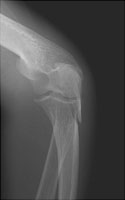

- Click on the image for a larger versionALateral radiograph of the elbow. The typical appearance of an olecranon fracture. The triceps tendon has distracted the fracture fragments.

Olecranon fractures result from a direct fall onto a flexed elbow. As the triceps inserts upon the olecranon, most olecranon fractures tend to be displaced. These fractures are not generally comminuted.